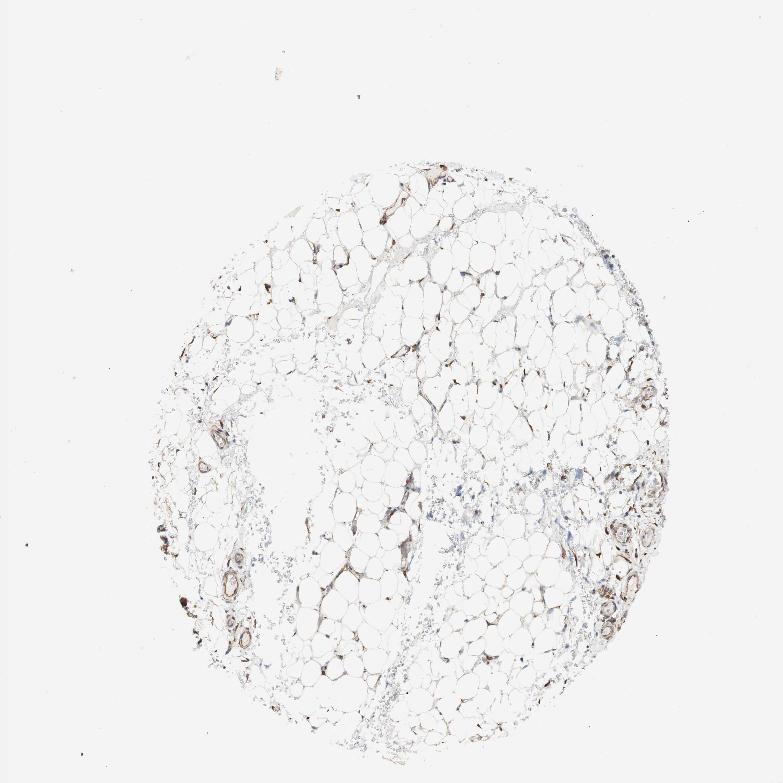

SOFT TISSUE 1 - Antibody stainingi

Antibody staining in the annotated cell types in the current human tissue is reported as not detected, low, medium, or high, based on conventional immunohistochemistry profiling in selected tissues. This score is based on the combination of the staining intensity and fraction of stained cells.

Each image is clickable and will lead to virtual microscopy that enables deeper exploration of all samples and also displays staining intensity scores, fraction scores and subcellular localization as well as patient and tissue information for each sample.

Antibody HPA011811

Chondrocytes Not detected

Fibroblasts Low

Peripheral nerve Low